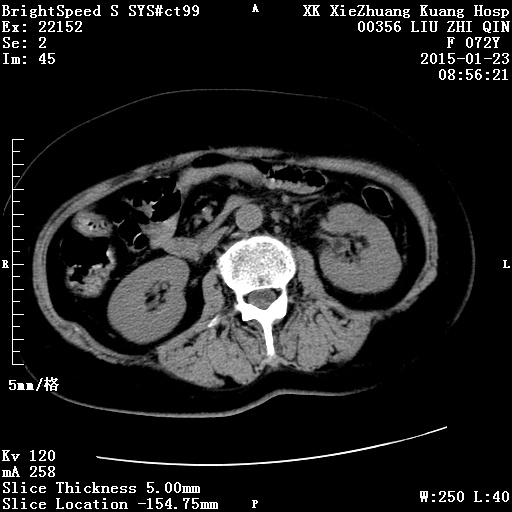

CT49815:肾上腺

本帖最后由 cefcmj 于 2015-1-23 19:53 编辑 腹痛,腹胀,恶心,腰背痛2月余。胸部及盆腔无异常。化验室检查无有价值表现。无明显内分泌临床症状。 ...

双侧肾上腺嗜铬细胞瘤恶变

双侧肾上腺转移瘤

考虑肾上腺转移瘤可能

考虑胃癌肾上腺转移

双侧肾上腺嗜铬细胞瘤恶变可能。